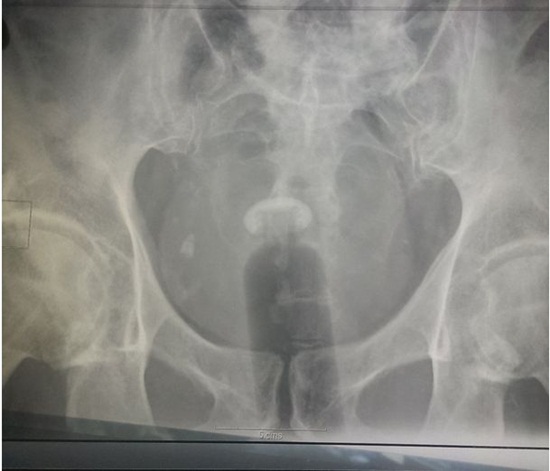

มาดูภาพเอกซเรย์ สารพัดสิ่งของที่เคยหลุดเข้าทวารหนัก

เผยภาพเอกซเรย์สุดอึ้ง สารพัดสิ่งที่เคยหลุดเข้าไปภายในทวารหนักผู้ป่วยทั่วโลก แปลกพิสดารกันจริง ๆ

การยัดสิ่งของต่าง ๆ เข้าไปในทวารหนักนั้น ไม่ว่าจะด้วยเหตุผลเพื่อหลบซ่อนการตรวจของเจ้าหน้าที่ทางการ หรือเป็นความผิดพลาดจากการแก้ขัดเมื่อเกิดอารมณ์ทางเพศก็ตาม สิ่งของที่หลุดเข้าไปนั้นล้วนแล้วแต่สร้างอันตรายให้กับอวัยวะภายในของผู้ป่วยได้หมด แต่ถึงจะเป็นอย่างนั้น เคสทางการแพทย์ว่าด้วยเรื่องของสิ่งแปลกปลอมที่หลุดเข้าไปในทวารหนักก็ยังมีให้เห็นอยู่เรื่อย ๆ ถมเถ แต่ละอย่างทำเอาอึ้ง ทึ่ง แบบไม่คิดว่ามันจะหลุดเข้าไปในทวารหนักได้จริง ๆ ดังเช่นตัวอย่างเคสที่เรานำมาฝากกันในวันนี้..